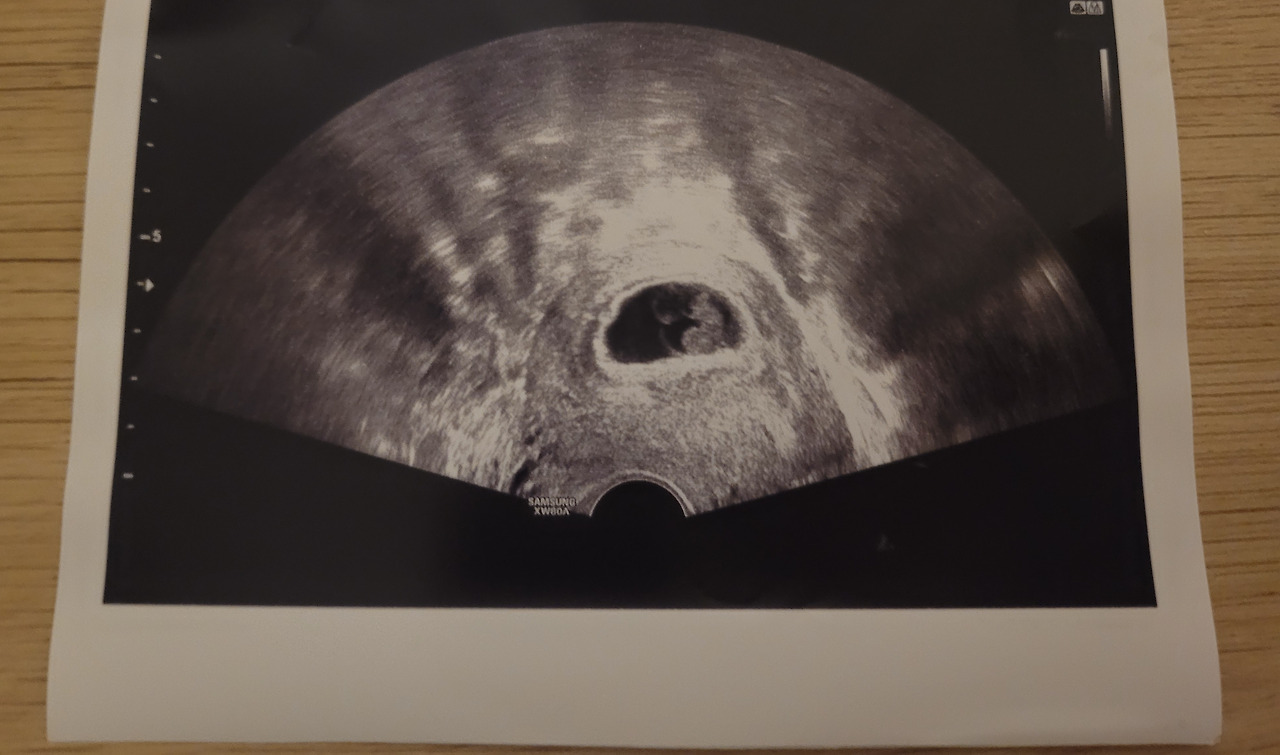

진료의뢰서와 피 검사지 안에 작은 종이가 있었다.

아기의 마지막 초음파 사진이었다.

난임병원 의사 선생님께서 직접 주진 않고 봉투에 넣어주셨나 보다. 작은 배려에 너무 감사했다.

"크기를 보면 7주 4일 정도 됐어요. 지금이 9주 0일이잖아요. 보통 2주면 자연배출이 되는데 아직까지 있으니까 4일 안에는 결정해야 할 것 같아요. "

7주 2일째에 우렁차게 뛰는 심장소리를 들었었다. 그런데 그 후 얼마 되지 않아서 아이의 심장이 정지했다니...... 몰랐다. 아이가 잘 자라는 줄만 알았다.